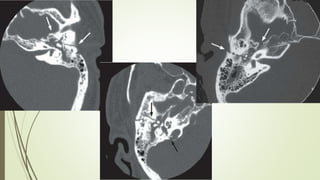

Evaluación Imagenologica

• #49 Izq: Sutura timpanoescamosa, hace mímica de frafctura Centro y derr. Sutura occipitomastoidea

• #50 IZQ: Sutura esfenoescamoosa,, lateral al foarmen espinoso(punta de flecha) DDER: sutura esfenopetrosa: foramen oval(astericos), trompa eustaqui (punat negra)

• #51 IZQ: Canal arqueado(petromastoideo) . Canal SC superior DER: Hiato del facial(blanca), ganglio geniculado (negra)